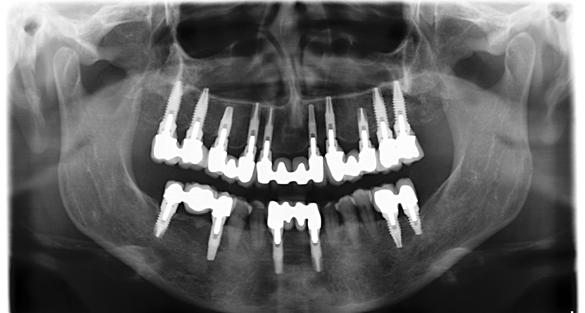

Figura 1. Radiografía inicial de la paciente. Se observa edentulismo total superior, a excepción del molar del primer cuadrante, indicado para exodoncia. En la mandíbula se aprecia pérdida ósea horizontal generalizada secundaria a la evolución de la enfermedad periodontal.

En la radiografía inicial (Figura 1) se observa la pieza 17 con pérdida ósea significativa, así como una reabsorción ósea homogénea a lo largo de todo el arco superior. En la arcada inferior se aprecia pérdida ósea horizontal generalizada y defectos localizados, como una lesión en cuña en la pieza 46. Ante esta situación, se decide realizar la exodoncia del molar remanente del

arco superior y planificar una rehabilitación implantosoportada para todo el maxilar superior, así como para el extremo distal del tercer cuadrante.

En los cortes del cone-beam de planificación se observa la posibilidad de colocar implantes estrechos en la zona anterior del maxilar, así como implantes de mayor diámetro y longitud en los sectores posteriores (Figura 2).

El mantenimiento periodontal y la implicación de la paciente en las medidas de autocuidado se mantuvieron de forma constante durante 23 años (Figura 25). La ortopantomografía realizada en una de las visitas de control mostró estabilidad completa de los implantes, sin signos radiográficos de pérdida ósea patológica.